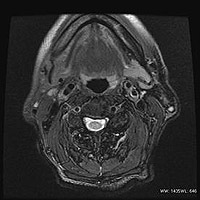

AIR Recon DL画像の一例

脳

頚動脈プラーク